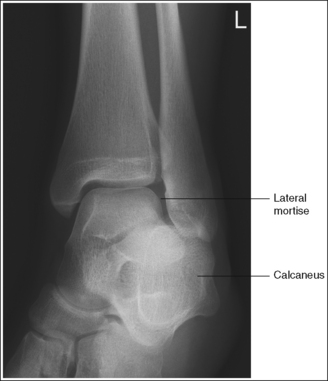

See Figure 6-46 and Box 6-10.

The ankle is demonstrated in an AP projection. The medial mortise (tibiotalar articulation) is open, and the distal tibia and talus are superimposed over the distal fibula by a small amount (0.125 inch [3 mm]), closing the lateral mortise (fibulotalar articulation).

See Figures 6-49, 6-50, and 6-51 and Box 6-11.

Mortise (15 to 20 degrees oblique): The ankle demonstrates 15 to 20 degrees of obliquity. The distal fibula is demonstrated without talar superimposition, demonstrating an open lateral mortise (talofibular joint), and the lateral and medial malleoli are in profile. The fibula demonstrates slight (0.125 inch [33 mm]) tibial superimposition.